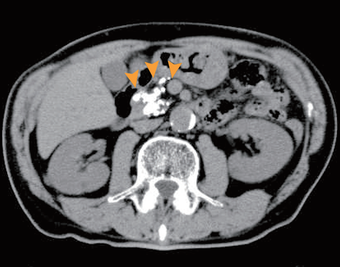

【進行した慢性膵炎、膵石症】

膵臓全体に膵石が多発している。